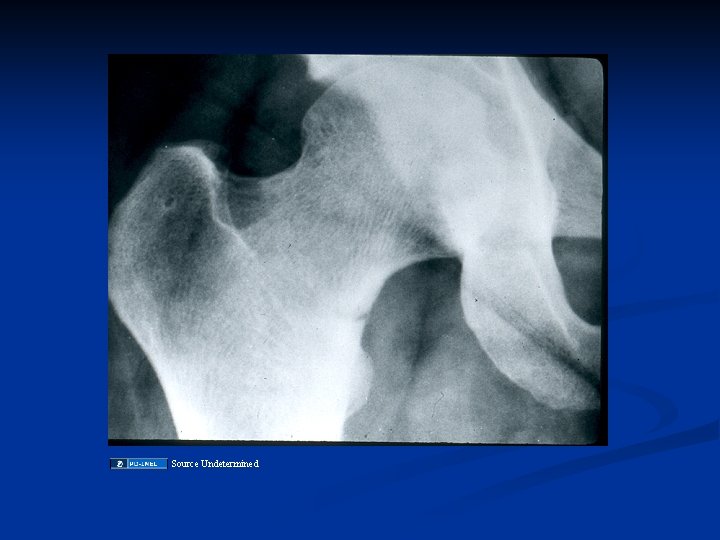

RICKETS, OSTEOMALACIA XRAY FINDINGS: OSTEOMALACIA Loosers zones - incomplete stress # with healing lacking calcium, on compression side of long bones. Codfish vertebrae due to pressure of discs Trefoil pelvis, due to indentation of acetabulae stress #s

OSTEOMALACIA: CLINICAL MANIFESTATIONS n Late hypocalcemia n Pseudofractures n In children, bowing of the legs and rachitic rosary, short stature